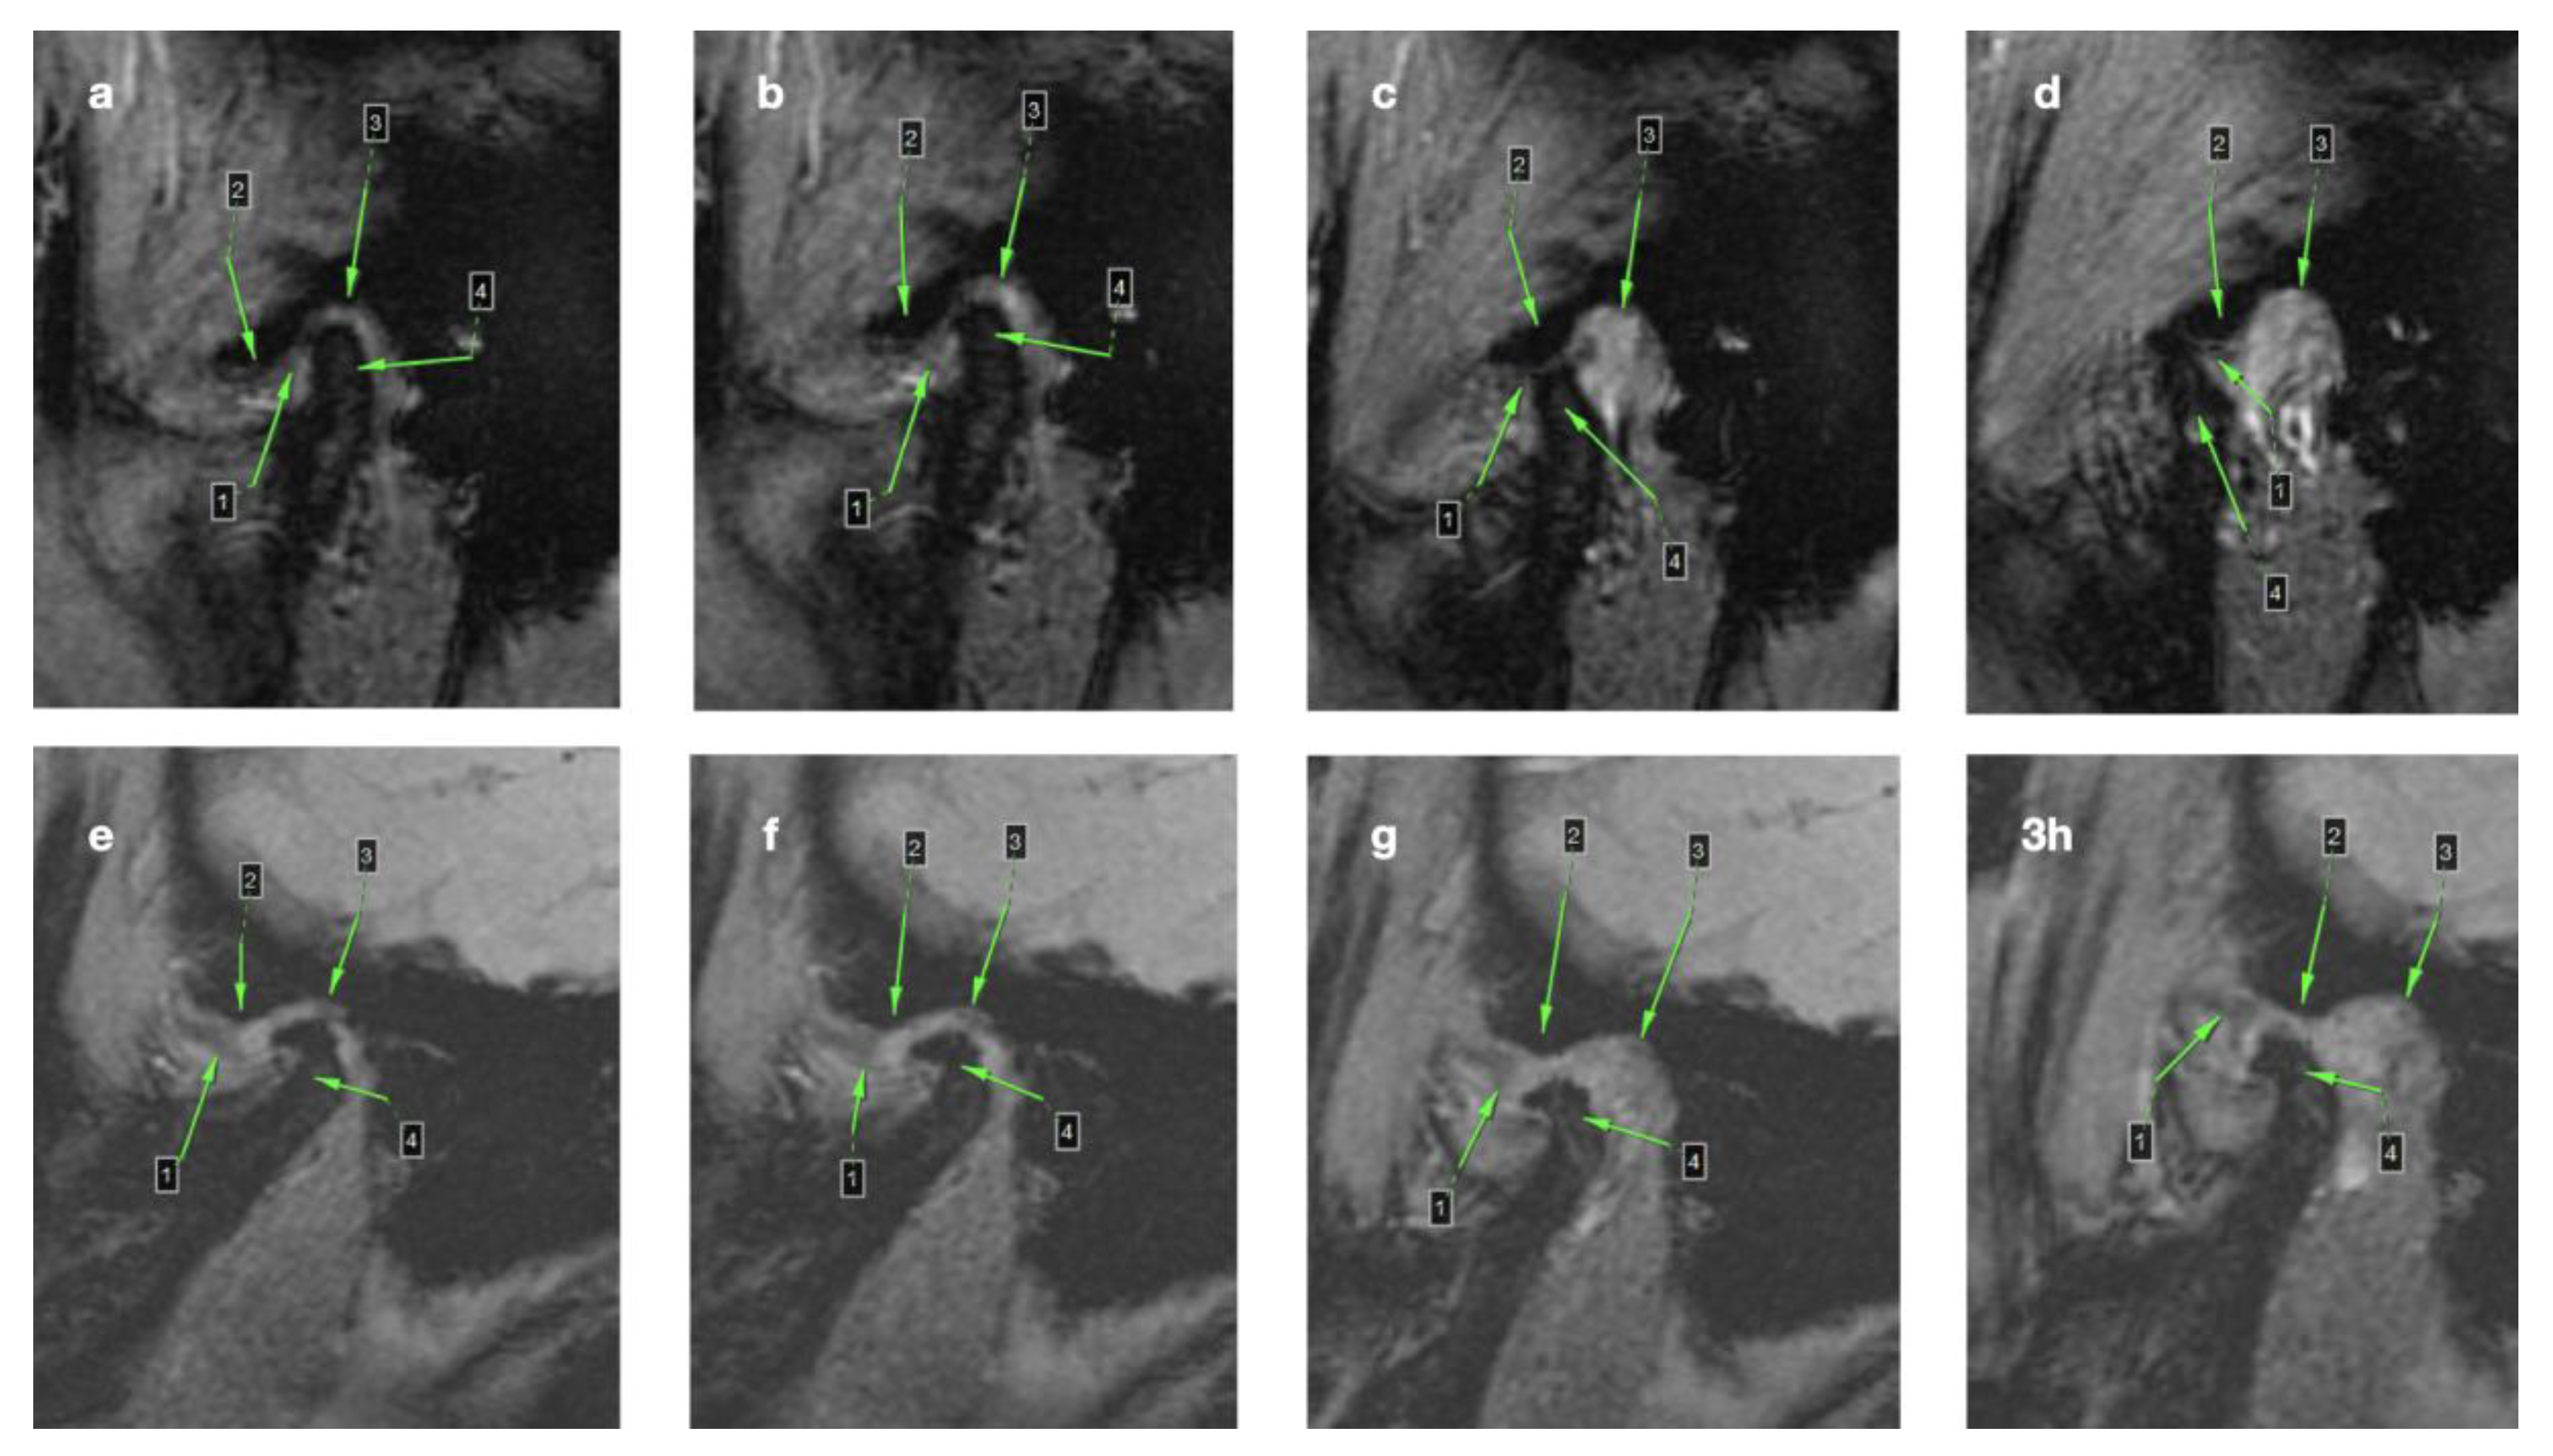

3.1. Magnetic Resonance Imaging (MRI)